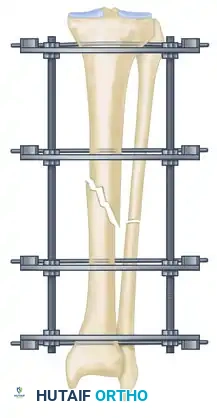

The management of complex, comminuted, or open tibial shaft fractures presents a formidable challenge to the orthopedic surgeon. The Ilizarov external fixation system, pioneered by Professor Gavriil Ilizarov, revolutionized the treatment of these injuries by introducing the concept of the tension-stress effect. Unlike rigid internal fixation, the Ilizarov circular frame utilizes tensioned fine wires to provide exceptional shear and torsional stability while permitting controlled axial micromotion. This unique biomechanical environment stimulates robust secondary bone healing (callus formation) without the need for extensive soft tissue stripping at the fracture site.

- Hold the frame in the desired position and insert proximal and distal transverse reference wires. These wires must be placed parallel to the knee joint line (proximal) and the ankle joint line (distal).

- As these reference wires are secured to the frame and tension is applied, initial correction of the fracture in the coronal plane is achieved.

- Eccentrically tilt the proximal and distal rings until they are perfectly parallel to the knee and ankle joints, respectively.

- After securing fixation with at least two tensioned wires to both the proximal and distal rings, adjust the threaded rods to bring these two rings parallel to their counterparts in the center of the frame. This maneuver facilitates further indirect fracture reduction.

Step 4: Eliminating Residual Distraction

Following multi-planar correction, it is imperative to assess the fracture site for any residual longitudinal distraction. Distraction gaps inhibit secondary bone healing and lead to nonunion. Adjust the longitudinal threaded rods to compress the fracture site and eliminate any residual distraction.